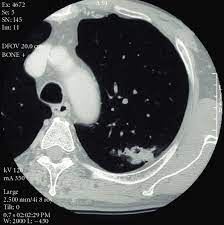

Currently, lung cancer is one of the deadly diseases in the world. Over time is a sign that it could be a cancer. Various investigations are underway to reduce this disease. Computed tomography scan (ct or cat scan). When you need them—and when you don't. If you do have these symptoms, see your doctor. Sclc can appear as segmental or lobar atelectasis with or without an obvious hilar mass. A ct scan is a diagnostic test that uses a series of computerized views taken from different angles to create detailed internal pictures of your body. This may reveal an obvious mass, the widening of. Screening rules applied to the plco and nlst cohorts. Learn who should take the test and who should not. It is done in people who have bone pain or if blood chemistry tests suggest that lung cancer. Ct scan of the cervical spine.

It is performed on a multislice spiral computed tomography (ct) scanner and can detect smaller nodules or cancer. The scan is painless and takes about 10 to 30 minutes. A radiographer operates the scanner. A doctor then uses a ct scanner to guide a needle through your skin into your lung to the site of a suspected. Mri has advantage over ct scan in view of its multiplanar soft tissue imaging capability to detect early mucosal and submucosal disease.

Ct scans to find lung cancer in smokers. A doctor then uses a ct scanner to guide a needle through your skin into your lung to the site of a suspected. Currently, lung cancer is one of the deadly diseases in the world. Ct scans expose you to radiation, which has been linked to cancer. ■ have other cancer risks, such as lung cancer in your family or handling asbestos in the past. Lung cancer is one of the most common and serious types of cancer. Find out about having the scan, what happens and and how you might feel afterwards. Performing a chest radiograph is one of the first investigative steps if a person reports symptoms that may be suggestive of lung cancer. Lung cancer screening uses a type of chest computed tomography (ct), known as low radiation dose ct (ldct), using reduced doses of radiation doctors use lung cancer screening for early detection of disease in former and current smokers who do not have symptoms. Radiological scan is useful in detecting early npc. The scan only takes a few minutes and is not painful. If you do have these symptoms, see your doctor. Another name for ldct is.

Ct scans expose you to radiation, which has been linked to cancer.